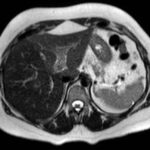

En este caso, presentamos una paciente femenina de 43 años de edad con antecedente de uso de ACO, a quien se le diagnosticó Trombosis portal mediante TC de abdomen c/cte. EV y trombofilia con mutación en el factor II de protrombina 20210, con evolución favorable.

Paciente femenina de 43 años, antecedente de obesidad grado I. Medicación habitual uso de ACO. Antecedente quirúrgico: una cesárea. Presenta cuadro clínico caracterizado por epigastralgia súbita de moderada intensidad. Se automedica con Buscapina sin mejoría del cuadro, por lo que acude a guardia. Le realizan TC y la derivan con diagnóstico de trombosis portal de la rama izquierda.

Se solicita nueva tomografía para descartar progresión de la trombosis y se vuelve a instaurar analgesia y anticoagulación EV.

Hallazgos imagenológicos